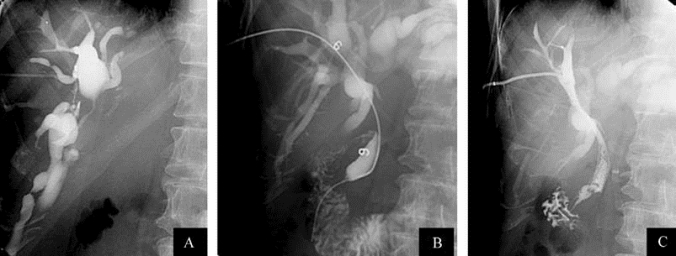

1.7.20.2.1(一)经内镜逆行胆胰管造影术

1.7.20.2.3(三)内镜下胆管取石

1.7.20.2.4(四)内镜下胆管引流术